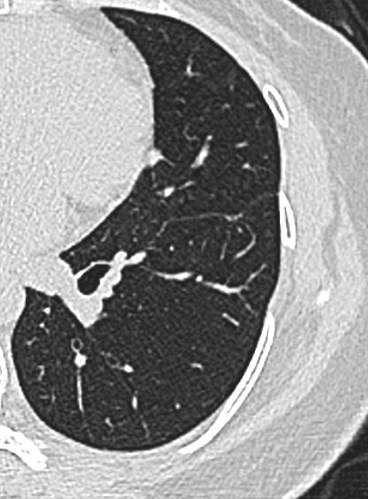

23年初复查CT左下肺GGO有所增大,直径:6.9mm

img

问题来了,一年多后复查GGO有增大,考虑恶性吗,需要手术吗,病理考虑什么?